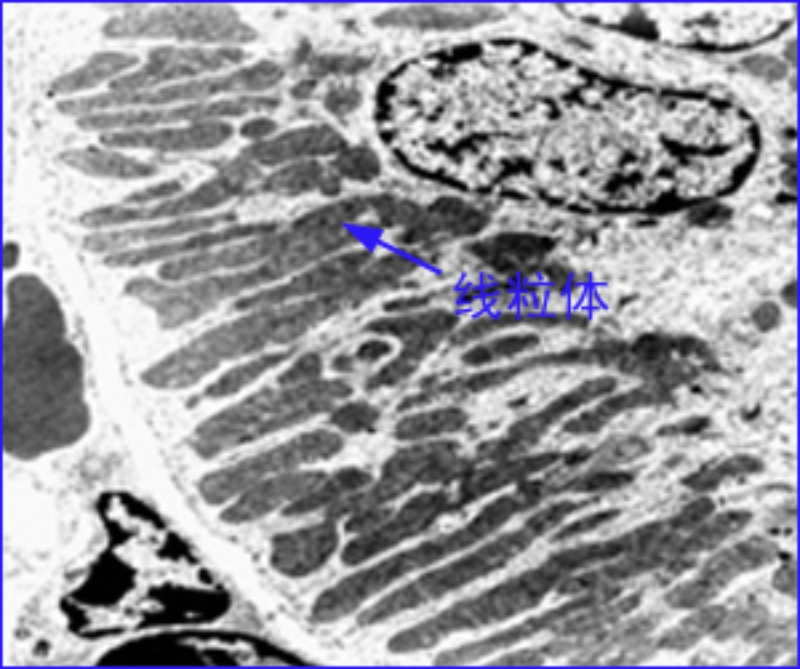

照片名称:46近曲小管

近端小管曲部

图中所示,近曲小管上皮细胞的病变为